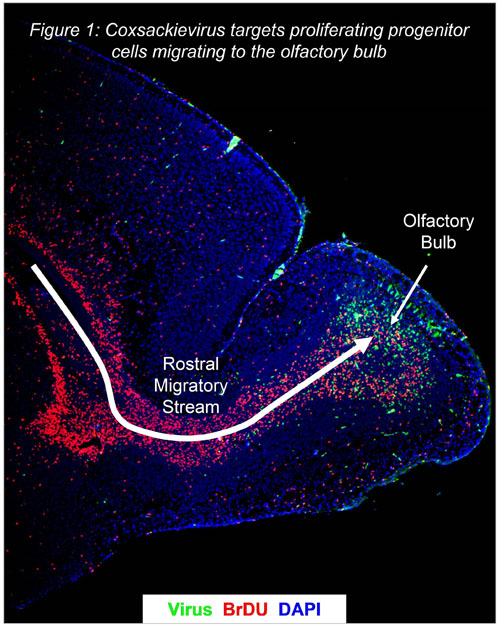

I am a viral immunologist focusing on persistent RNA virus infections associated with human disease. My interests include the study of host – viral pathogen interactions and the activation of the innate and adaptive immune response during viral persistence. My current research includes an in vivo model of infection utilizing a pathogenic human strain of coxsackievirus B3 (CVB3) to better understand tropism, viral-mediated immunopathology, and the occurrence of autoimmune-like diseases in susceptible organs harboring persistent virus. Coxsackieviruses are ubiquitous pathogens which have been associated with a number of acute and chronic diseases in humans, including pancreatitis, myocarditis, diabetes, and aseptic meningitis. My latest findings indicate that CVB3 preferentially targets and injures neural stem cells eventually leading to developmental defects and chronic disease in the central nervous system. I hope to use the knowledge gained from these investigations to devise treatment and vaccine strategies in order to alleviate diseases initiated by CVB3 and other persistent viruses.